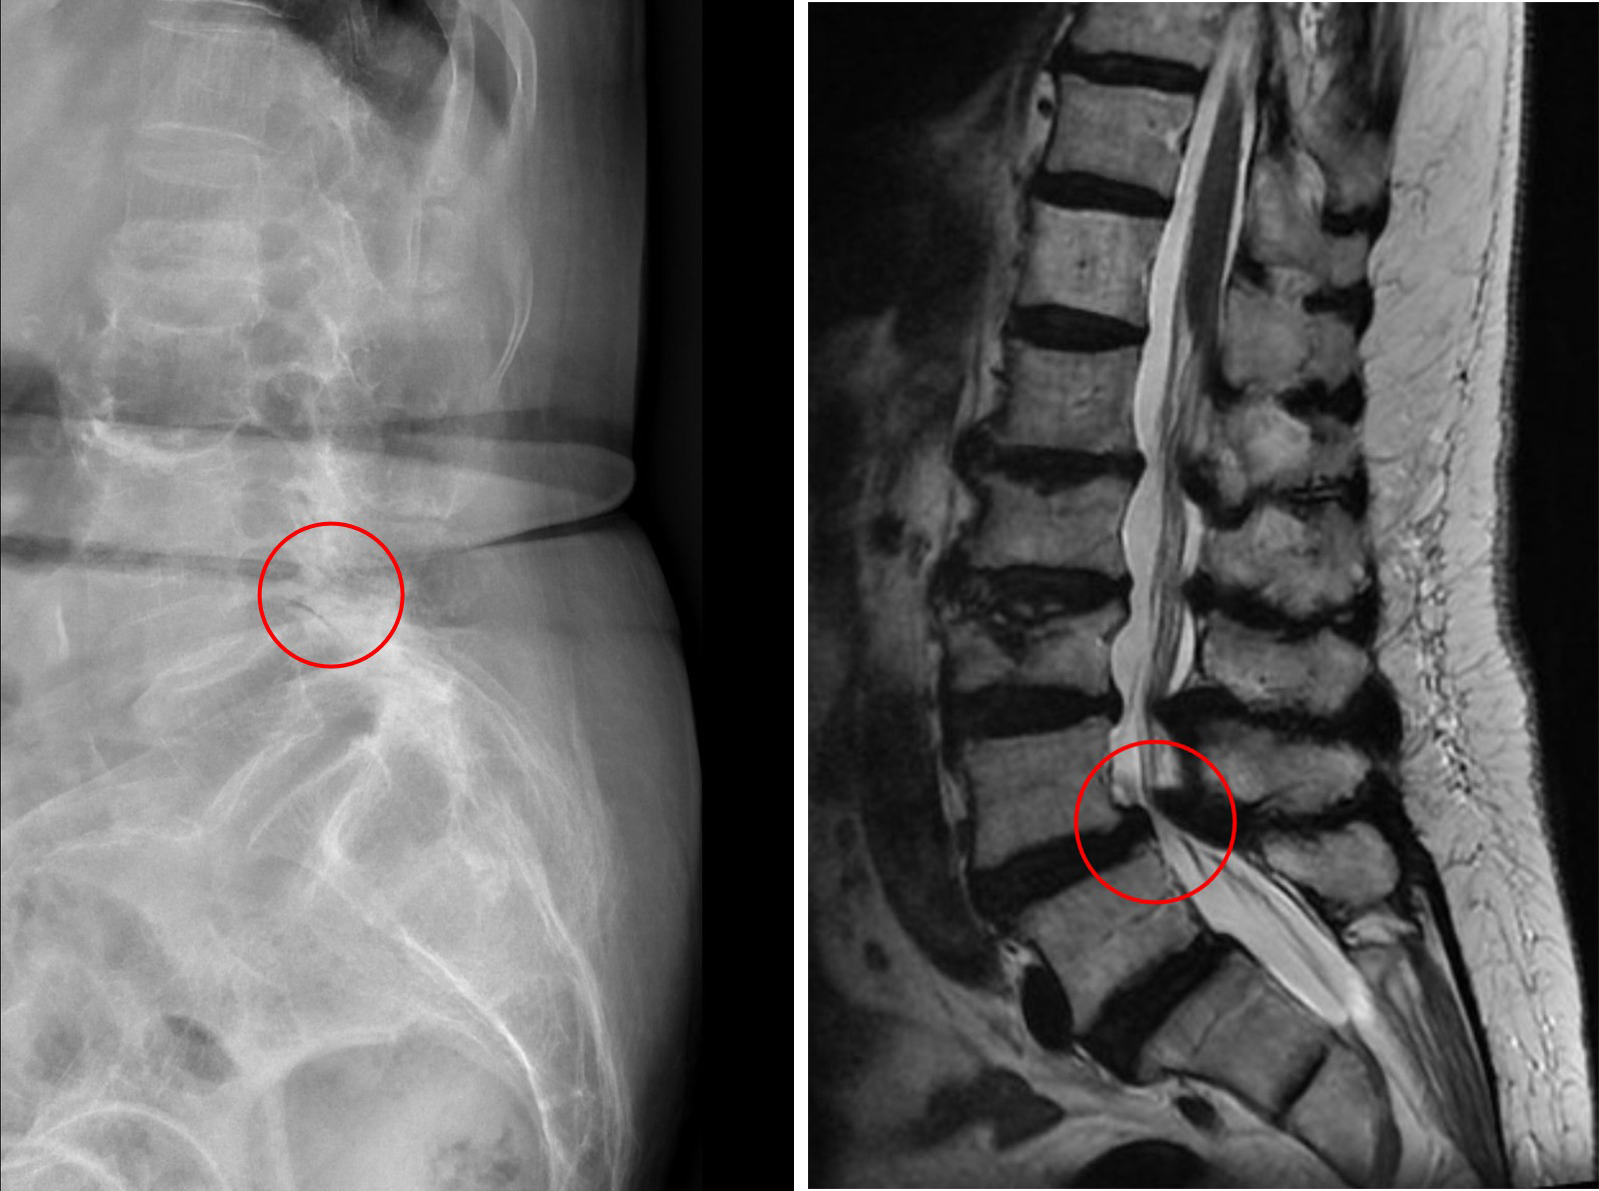

來自苗栗縣的81歲的郭奶奶,因腰痛、腿痛和腿麻嚴重影響行走能力,僅能靠輪椅代步,四處求醫無法改善,到花蓮慈濟醫院林欣榮院長門診,經核磁共振造影檢查發現有嚴重脊椎側彎及腰椎滑脫,轉介神經脊椎微創外科主任洪祥益。經謹慎評估風險並與家屬討論後,以微創融合手術治療,患者於術後隔天即可下床,順利擺脫輪椅,重回自如行動的生活。

經考慮患者意願,在與家屬溝通後,由麻醉團隊為患者安排心臟超音波、頸部超音波、神經傳導等檢查評估風險,洪祥益主任帶領團隊於十月底為患者進行微創腰椎融合手術,利用釘子將滑脫的脊椎矯正歸位,並把骨刺清除乾淨。